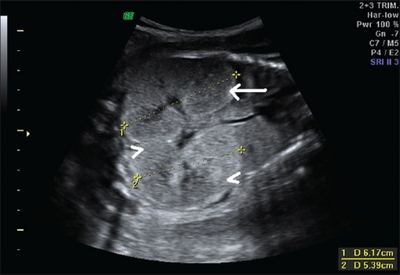

Ultrasonography is the primary method to evaluate autosomal recessive polycystic kidney disease, particularly in the perinatal and neonatal stages.[3]